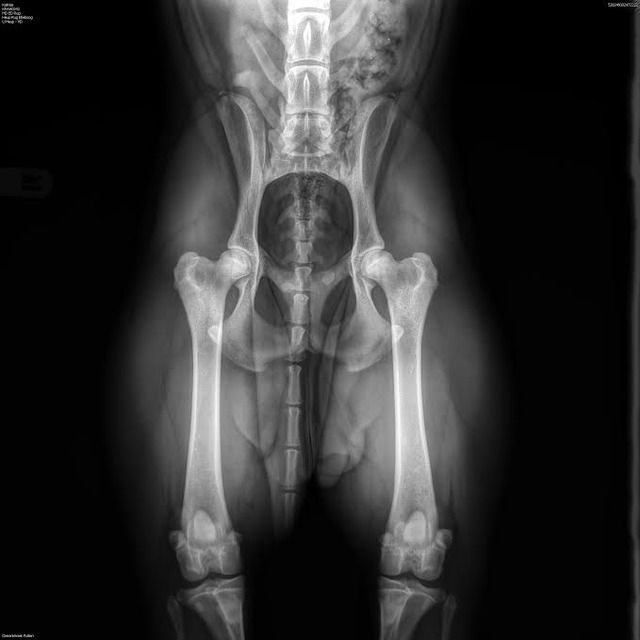

Voorgerontgend